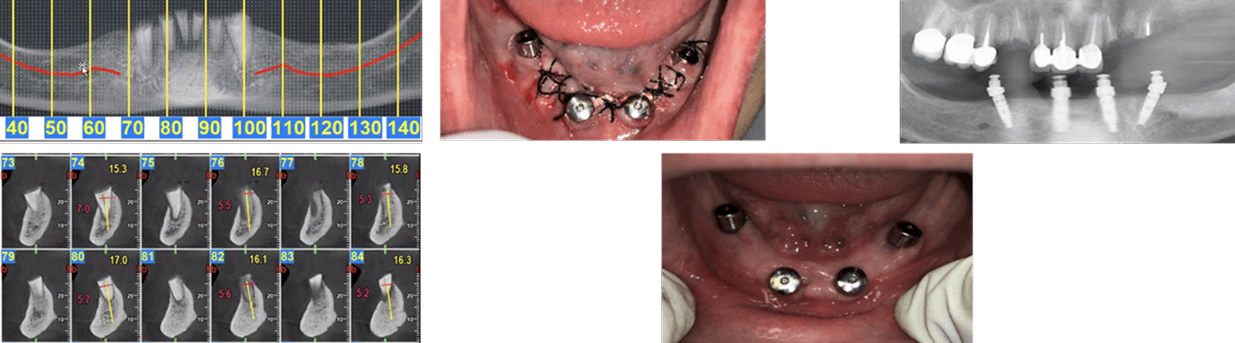

A 70-year-old heavy smoker presented with a fully edentulous mandible and clinically poor bone quality. Six implants were placed, each fitted with a MED healing abutment to enhance bone regeneration and support early osseointegration. Despite the compromised bone condition and smoking-related healing challenges, the patient demonstrated an excellent biological response throughout the recovery phase.

After only 45 days, radiographic assessment confirmed successful osseointegration across all six implants, allowing for full-arch prosthetic restoration. The patient received a stable mandibular bridge within a significantly shortened treatment period. The use of MED healing abutments contributed to rapid bone maturation, improved implant stability, and an accelerated rehabilitation process even in a high-risk, heavy-smoking patient.